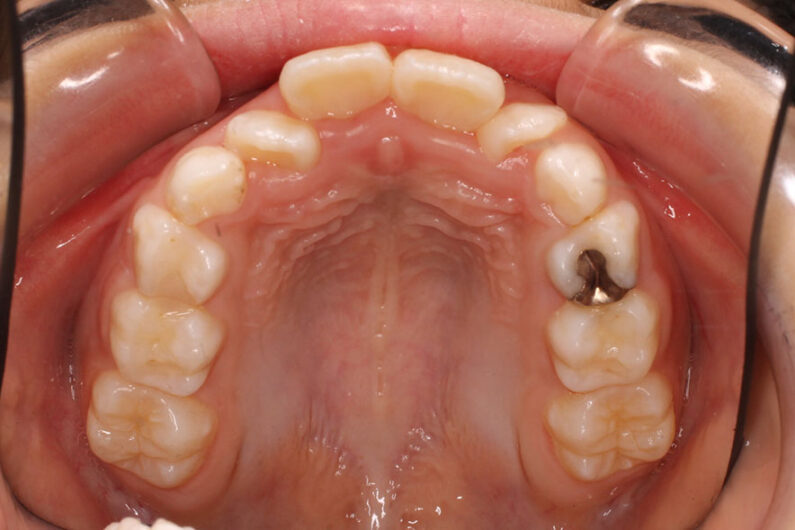

| 上下顎前突および前歯部に叢生(がたつき)がある患者さんです。 小児矯正で歯列の拡大を行った後、マルチブラケット装置での動的治療を開始しました。 口唇前突傾向改善のため、抜歯スペースを利用して治療しました。 抜歯スペースの方向に歯牙を移動させるため、前歯を前方傾斜させずに配列しています。 もし非抜歯で治療していたとしたら、また違った結果になっていたでしょう。 マルチブラケット装置での動的治療期間 2年4か月でした。 |